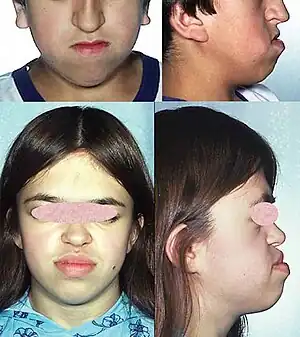

The brain is abnormally smooth, with fewer folds and grooves. The face, especially in children, has distinct characteristics including a short nose with upturned nares, thickened upper lip with a thin vermilion upper border, frontal bossing, small jaw, low-set posteriorly rotated ears, sunken appearance in the middle of the face, widely spaced eyes, and hypertelorism. The forehead is prominent with bitemporal hollowing.[3]

With the use of prenatal ultrasonographic imaging, early detection of abnormal brain development in the fetus with MDS can be seen. At birth, facial dysmorphism can be present in the infant. Young children, when affected, can have feeding difficulties, severe intellectual disability, developmental delay, and seizures. MRI facilitates early detection of this syndrome in children by revealing a "smooth brain" image, also called lissencephaly.[7] Children with this syndrome may remain underdiagnosed because of rarity and the prevalence of facial features that appear to be dysmorphic. The syndrome shares distinct external features (phenotype) similar to more common syndromes. Lack of relevant family history may delay diagnosis. FDNA provides a service that in turn increases the chances of detecting these distinct characteristics, which, when shown to a geneticist, can assist in reaching the right medical diagnosis. If a couple has had one child with MDS, they can be offered prenatal screening in future pregnancies. This option is particularly important for the 20% of MDS families where one parent carries a balanced chromosome rearrangement. The risk of these couples having another child with MDS depends on the exact type of chromosomal rearrangement present and may be as high as 25–33%. For families in which both parents' chromosomes are normal, the risk of having another child with MDS is low (1% or less). Either chorionic villus sampling (CVS) or amniocentesis can be used early in a pregnancy to obtain a small sample of cells from the developing embryo for chromosome studies. Early prenatal diagnosis by ultrasound is not reliable because the brain is normally smooth until later in pregnancy. Couples who are considering prenatal diagnosis should discuss the risks and benefits of this type of testing with a geneticist or genetic counselor.